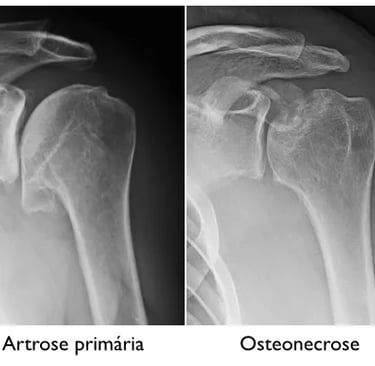

Artrose do Ombro

A artrose (também chamada de osteoartrose ou osteoartrite) é a degeneração da superfície cartilaginosa de uma articulação. A articulação, que normalmente deve ser congruente, bem lubrificada e com as superfícies lisas, possibilitando movimentos suaves, torna-se doente e incongruente.